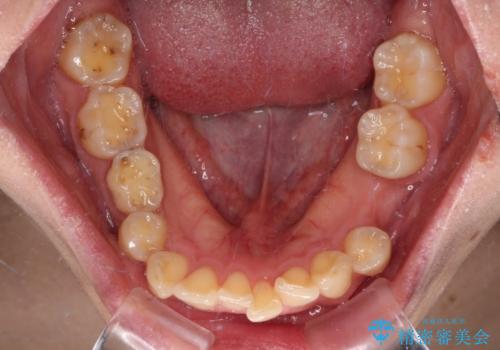

- 全体的なデコボコと左下乳歯部の欠損を気にして来院された患者様です。

乳歯が抜け落ちた後の後続永久歯が欠損しているため、スペースが残っておりました。

口元の突出感を気にしているのであれば欠損スペースを利用して抜歯矯正を行うことも可能ですが、横顔の印象はスッキリとしている状態であったため、矯正治療でスペースを閉じきることは不可能と判断し、インプラントによる補綴治療を行うこととしました。